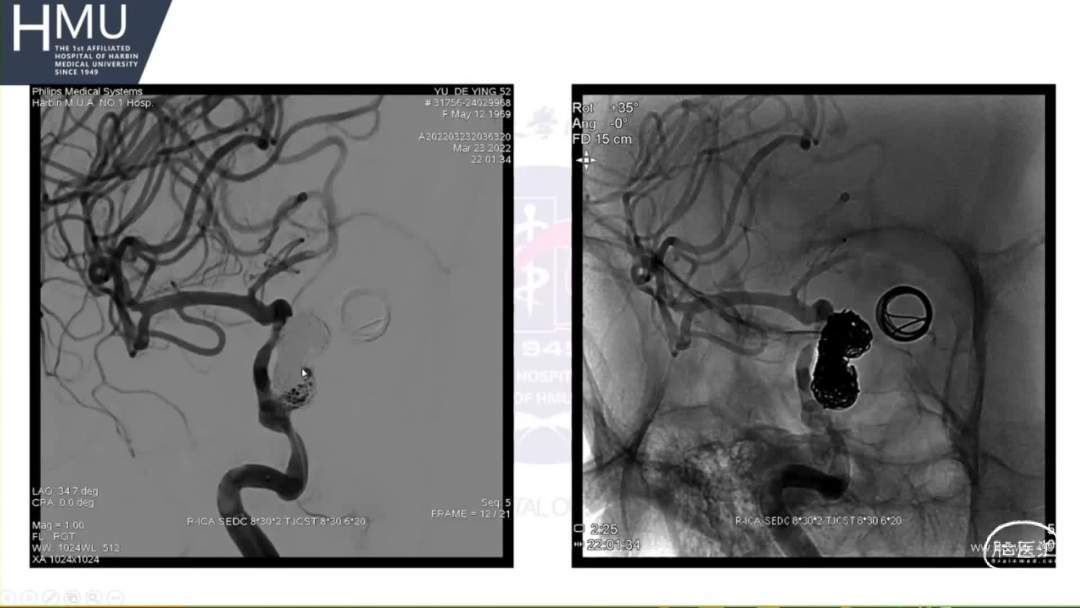

21:00覆膜支架置入术

海绵窦段动脉瘤如何导致蛛网膜下腔出血?